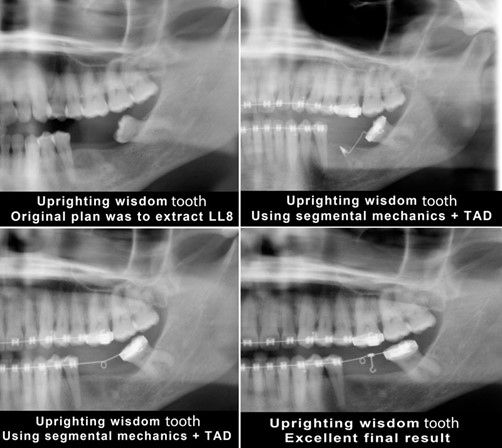

5. Upright mesially tilted second molas as well as third molars if needed.

You can place the infinity Temporary Anchorage Device TADs mesial or distal to upright the tilted tooth.

a. If you place the mini implant mesially, then you need a cantilever system to deliver the uprighting force as the case below

b. If you place the mini implant distally, then you need to use a power chain or a closed coil NiTi to deliver the upright force.